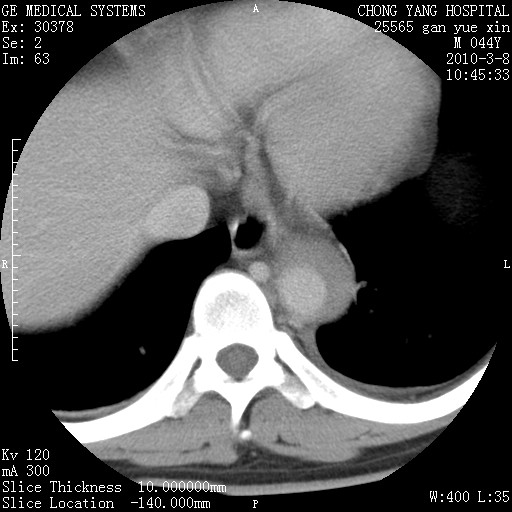

标题: CT24940:主动脉增强,典型病例。 [打印本页]

标题: CT24940:主动脉增强,典型病例。

夹层动脉瘤。

动脉夹层

夹层动脉瘤,典型

主动脉夹层。

动脉夹层的分型:

⒈debakey分型:根据主动脉夹层累及部位,分为三型:ⅰ型:原发破口位于升主动脉或主动脉弓部,夹层累及升主动脉、主动脉弓部、胸主动脉、腹主动脉大部或全部,少数可累及髂动脉。ⅱ型:原发破口位于升主动脉,夹层累及升主动脉,少数可累及部分主动脉弓。ⅲ型:原发破口位于左锁骨下动脉开口远端,根据夹层累及范围又分为ⅲa,ⅲb。ⅲa型:夹层累及胸主动脉。ⅲb型:夹层累及升主动脉、腹主动脉大部或全部。少数可累及髂动脉。

⒉stanford分型:a型:夹层累及升主动脉,无论远端范围如何。b型:夹层累及左锁骨下动脉开口以远的降主动脉。

夹层动脉瘤,少量胸水

夹层动脉瘤;左侧少量胸腔积液。

典型主动脉夹层。